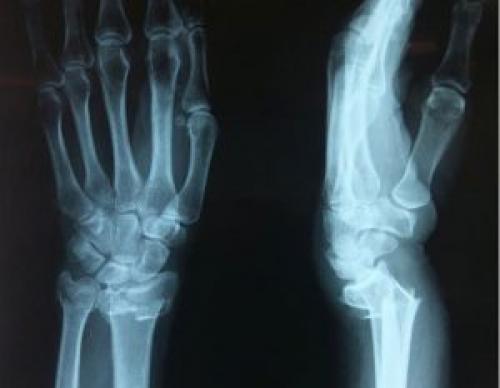

Перелом лучевой кости руки чаще всего случается при падениях с приземлением на дистальный отдел выпрямленной руки. Травма характерна для женщин старшего возраста, организм которых испытывает гормональную перестройку в связи с наступлением периода менопаузы. Нарушение целостности кости предплечья сопровождается острой болью, выраженным отеком и двигательной дисфункцией. Травма подтверждается результатами рентгенографии, лечится оперативным и консервативным способом.

Предплечье состоит из лучевой и локтевой кости. Несмотря на то, что локтевая кость в два раза толще, переломы лучевой кости встречаются гораздо чаще. Привычной локализацией является область около лучезапястного сустава. Диафизарные повреждения и травмы в области локтевого сочленения занимают 5% от общего числа случаев травматизации кости.

Полные переломы, когда лучевая кость разделена на две отдельные части, осложняются кровотечением и разрывом мышечных волокон, которые «растягивают» костные отломки, вызывая смещение. Неполными называют трещины кости и надломы.

В зависимости от анатомической локализации перелом лучевой кости делится на:

- диафизарные – в середине кости;

- повреждение головки и шейки лучевой кости внутри суставов;

- поражение шиловидного отростка.